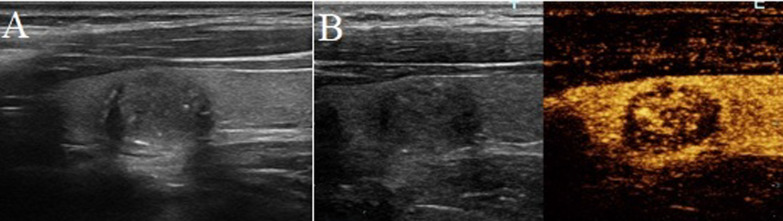

Fig. 1.

A papillary thyroid carcinoma in a 40-year-old woman. A Greyscale ultrasound showed that there was a halo surrounding the thyroid nodule. B Contrast-enhanced ultrasound revealed hypo-enhancement at peak, with a irregular low-enhancing ring (at the 20th second after the injection of contrast agent)